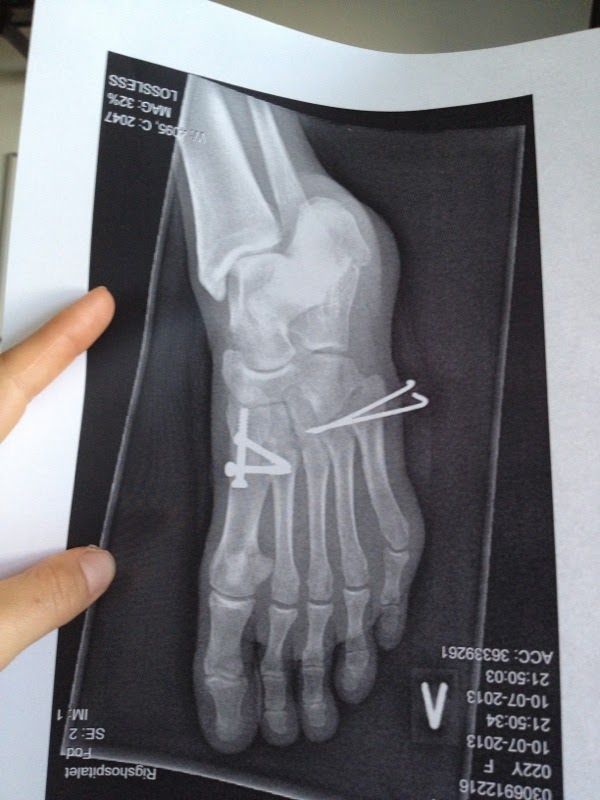

Vigtigst af alt så gik operationen dog godt. To overlæger rodede rundt i 2,5 time og fik samlet puslespillet og fikseret det med tre skruer og to K-tråde, der stak ud af siden på foden. Lidt markabert!